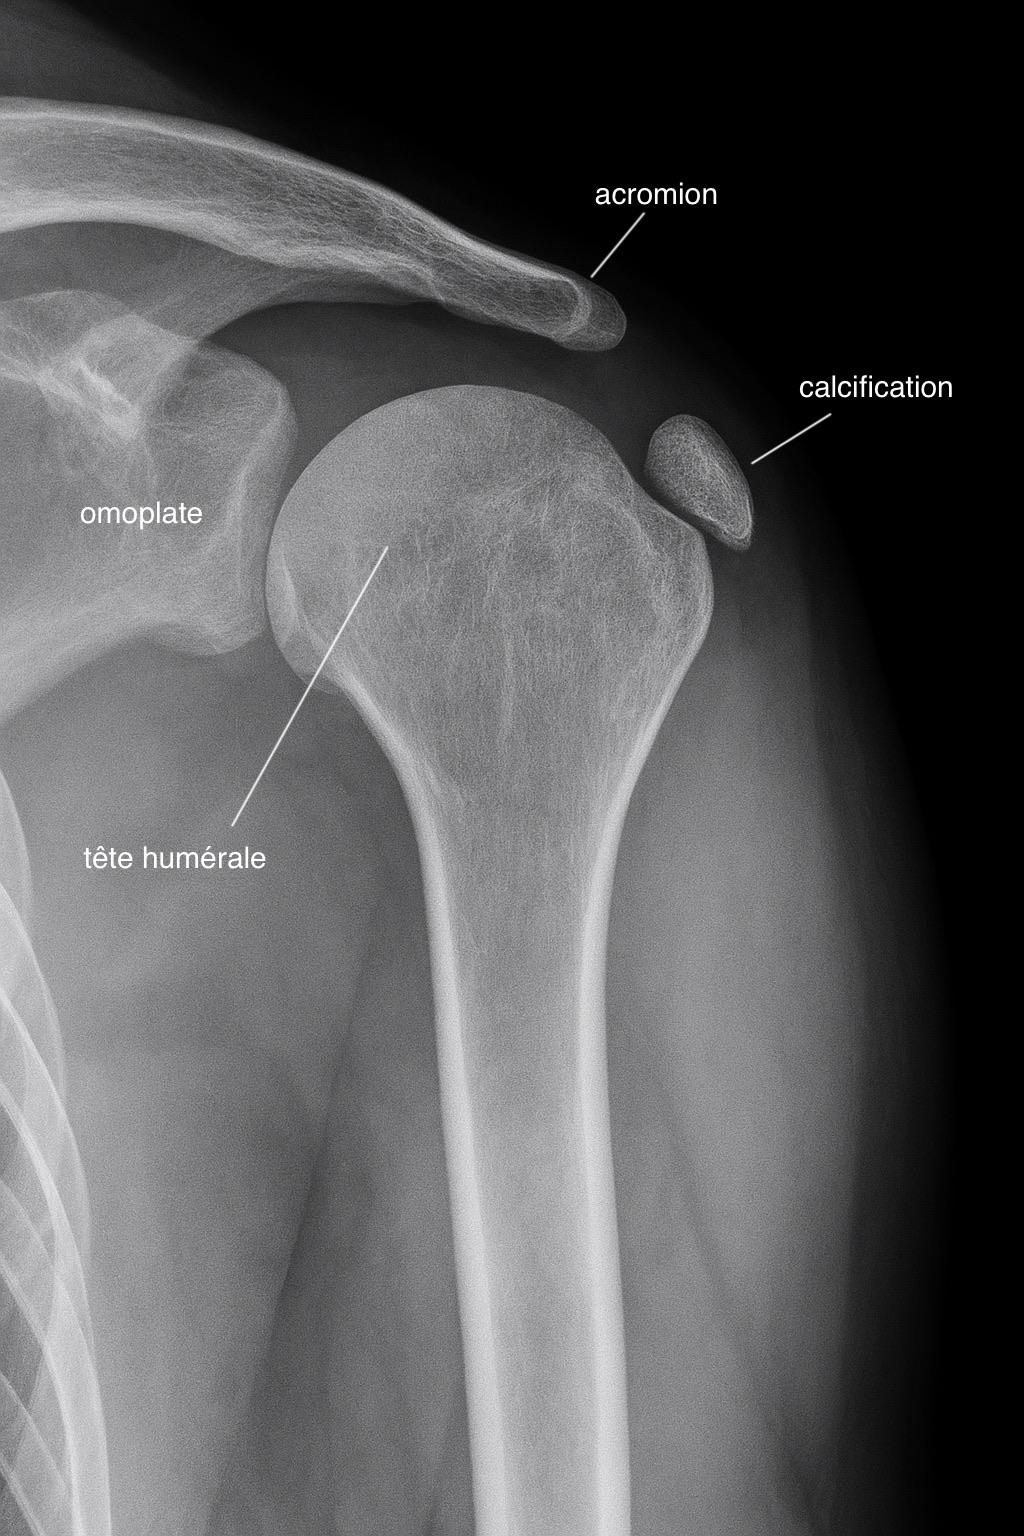

Anatomie des calcifications de l'épaule - Illustration médicale détaillée

Dépôts calciques dans les tendons de la coiffe des rotateurs

Les calcifications de l'épaule correspondent à des dépôts de calcium au sein des tendons, le plus souvent le supra-épineux. Ces dépôts sont responsables de douleurs aiguës et de limitations fonctionnelles importantes.

Examen de référence pour visualiser les calcifications et évaluer leur taille et localisation